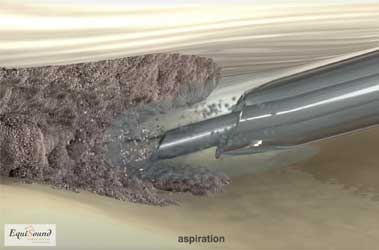

Tenex is een behandelingstechniek die 5j geleden ontwikkeld werd in USA om chronische peesaandoeningen te behandelen bij mensen (chronische achillespezen, hielspoor, patellapeesdegeneratie etc). De techniek maakt gebruik van ultrason geluid (zoals bij het verwijderen van tandsteen) om beschadigd weefsel af te breken en zo het genezingsproces te stimuleren en een nieuwe herstelkans te geven. De geluidsfrequentie is specifiek gekozen om enkel harde weefsels (fibrose en mineralisaties) af te breken en geen schade aan te brengen aan gezond peesweefsel. De ultrason behandeling wordt toegediend door middel van een holle naald in een holle buis (zie foto 9a). Uit de holle naald komt tijdens de behandeling een influx van NaCl dewelke tegelijk geaspireerd wordt door de holle buis (foto 9b en 9c). Het water zorgt in eerste instantie voor de afvoer van gedebrideerd weefsel, maar tegelijk ook voor afkoeling van de naald dewelke erg opwarmt door het ultrason proces.

Doordat de naald echogeleid ingebracht wordt via steekincisies in de huid, is deze behandeling minimaal-invasief. Zo recupereert de patiënt sneller en is er weinig wondzorg nodig. Ook zorgt dit voor een exacte plaatsing van de naald in het degeneratieve gebied van de pathologische structuur.